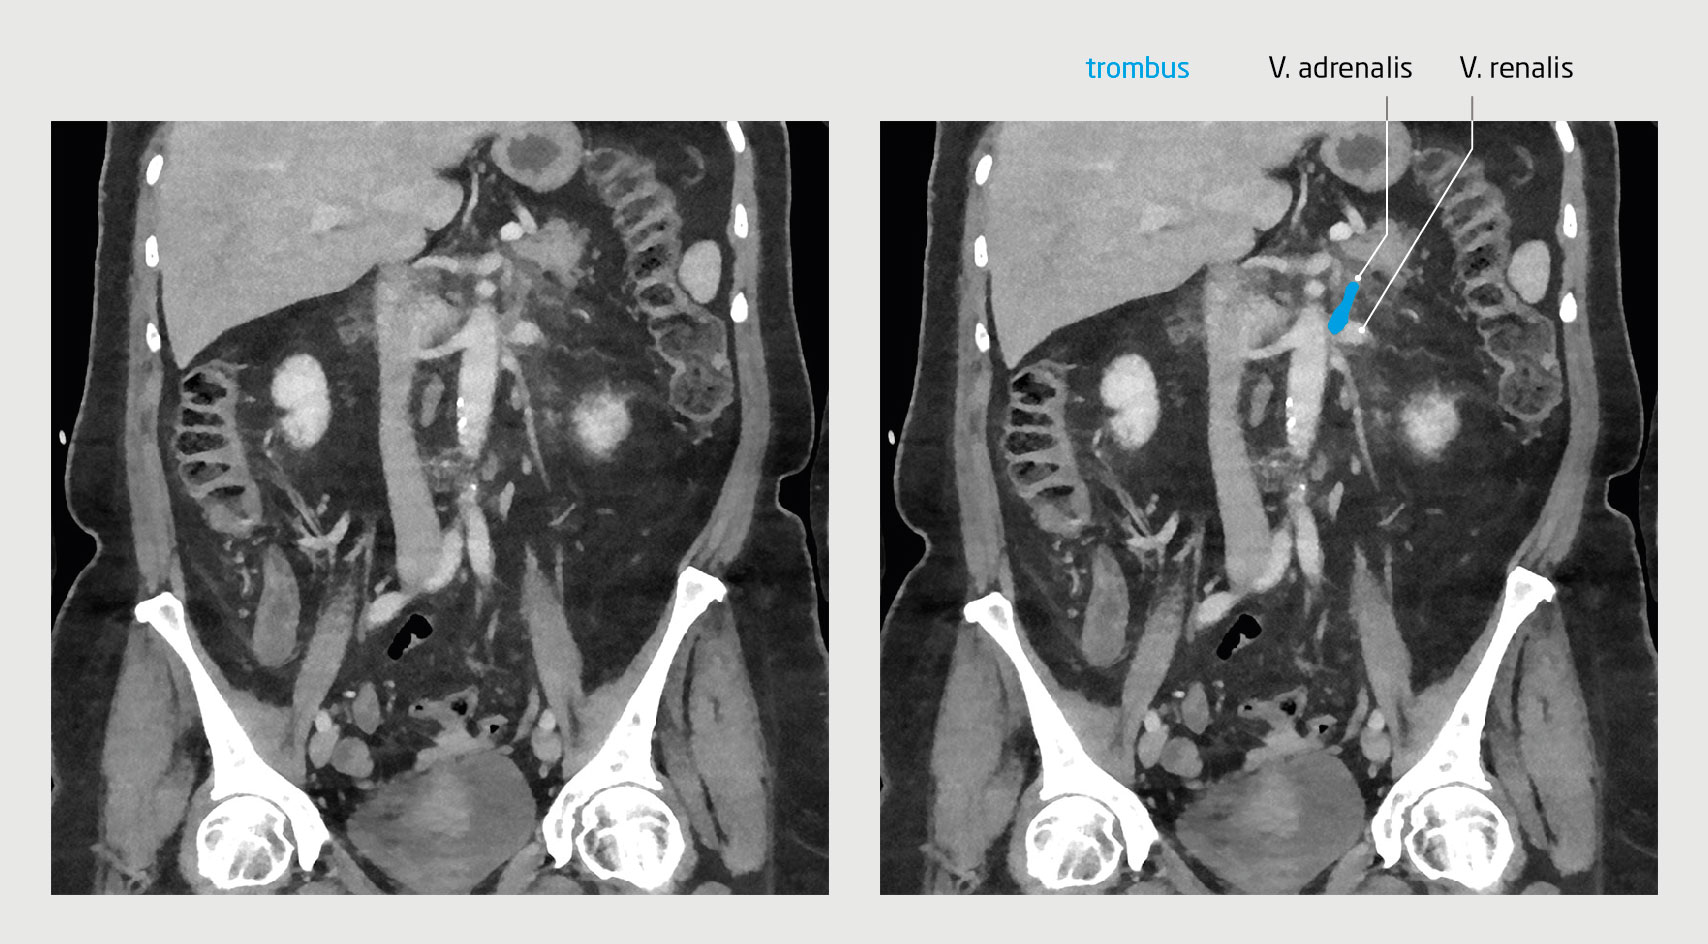

Figuur 1

Trombose van de V. renalis en V. adrenalis

Figuur 1 | Trombose van de V. renalis en V. adrenalis

Coronale CT-scan van het abdomen van een 63-jarige vrouw waarop na intraveneuze toediening van contrastmiddel trombose te zien is van de linker V. renalis en V. adrenalis.

Vanwege het klinisch beeld en het vermoeden van trombose na vaccinatie bepaalden wij geen D-dimeerconcentratie, maar verrichtten wij gericht beeldvormend onderzoek. Na intraveneuze toediening van contrastmiddel was op een CT-scan van het abdomen trombose te zien van de linker V. renalis en V. adrenalis (figuur 1). Een CT-scan van de hersenen met contrast toonde in de linker hersenhelft veneuze sinustrombose op de overgang van de sinus rectus naar de sinus transversus (figuur 2).